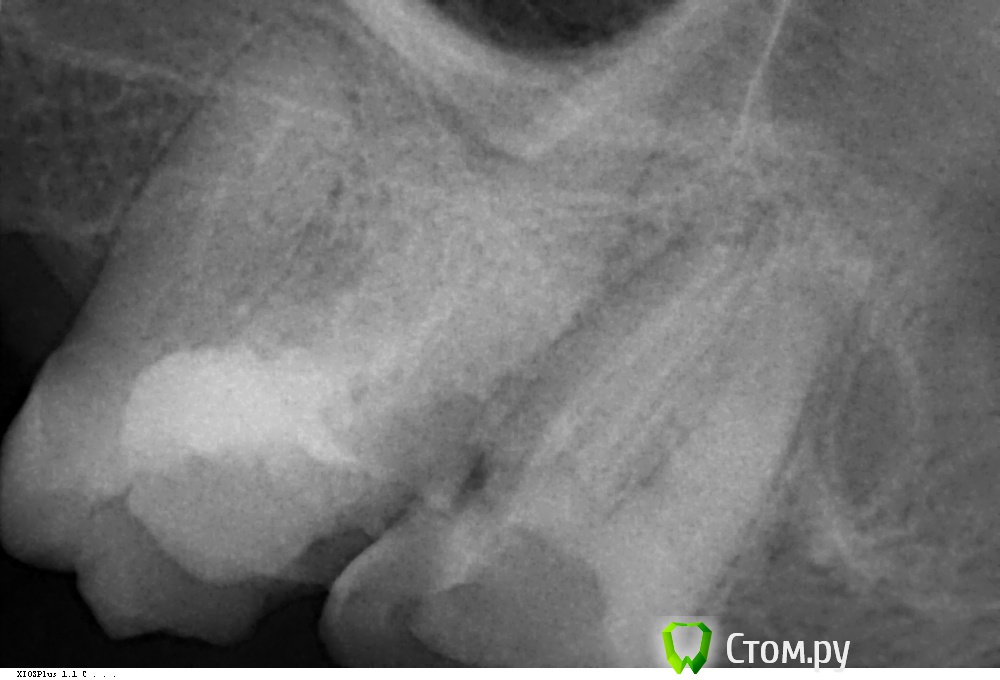

Очень прошу вас помочь в решение этого сложно для меня вопроса. Был в у двух стоматологов. Первый врач сделал осмотр без снимка и сказал, что есть перелом зуба т.к заметил качающийся несильно край и его однозначно необходимо удалить, второй смотрел исключительно по снимку и сказал, что перелома вроде нет ...

Это снимок коренного зуба, который обозначен на зубной карте как №7 (27).

На ощупь языком я определил где примерно качается край

Стрелочка 1: начало

Стрелочка 2: приблизительно конец

Скажите, пожалуйста, есть перелом или трещина, и какой метод лечения для этого зуба подходит?